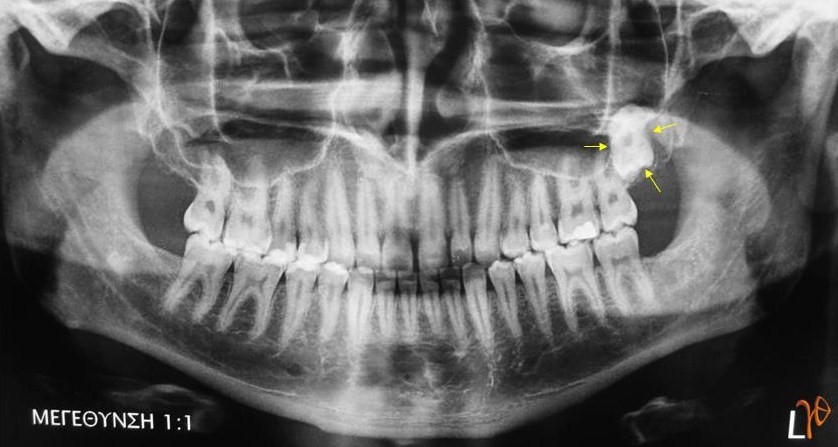

Οι πιο συχνές βλάβες στο στόμα είναι τα αποστήματα, τα οποία όταν οφείλονται σε μικροβιακές λοιμώξεις δοντιών της άνω γνάθου μπορούν να εκδηλώνονται και στην υπερώα (Εικόνα 3). Η θεραπεία τους προϋποθέτει την θεραπεία του υπεύθυνου δοντιού.

Εικόνα 3. α. Απόστημα που οφείλεται σε γομφίο οδόντα (βέλος), β. Απόστημα που οφείλεται σε τομέα οδόντα (βέλος).